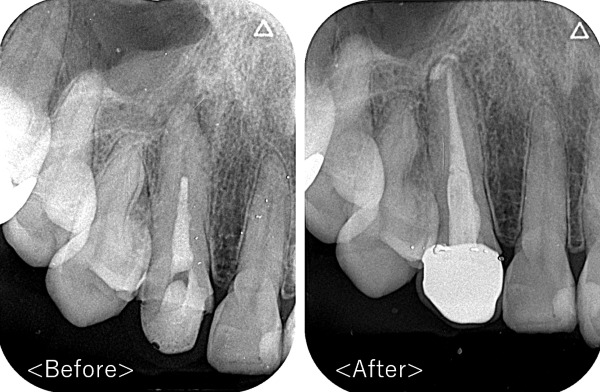

患者様は40代の男性で、『前歯がうずいて痛い』とのことでご来院されました。

レントゲン写真を確認したところ、歯の根の先に膿ができており、骨が溶けている事がわかりました。

こちらが術後のレントゲン写真になります。

患者様は噛んでも痛まなくなりました。

根の先端にできた膿も消失しており、骨が元に戻っています。